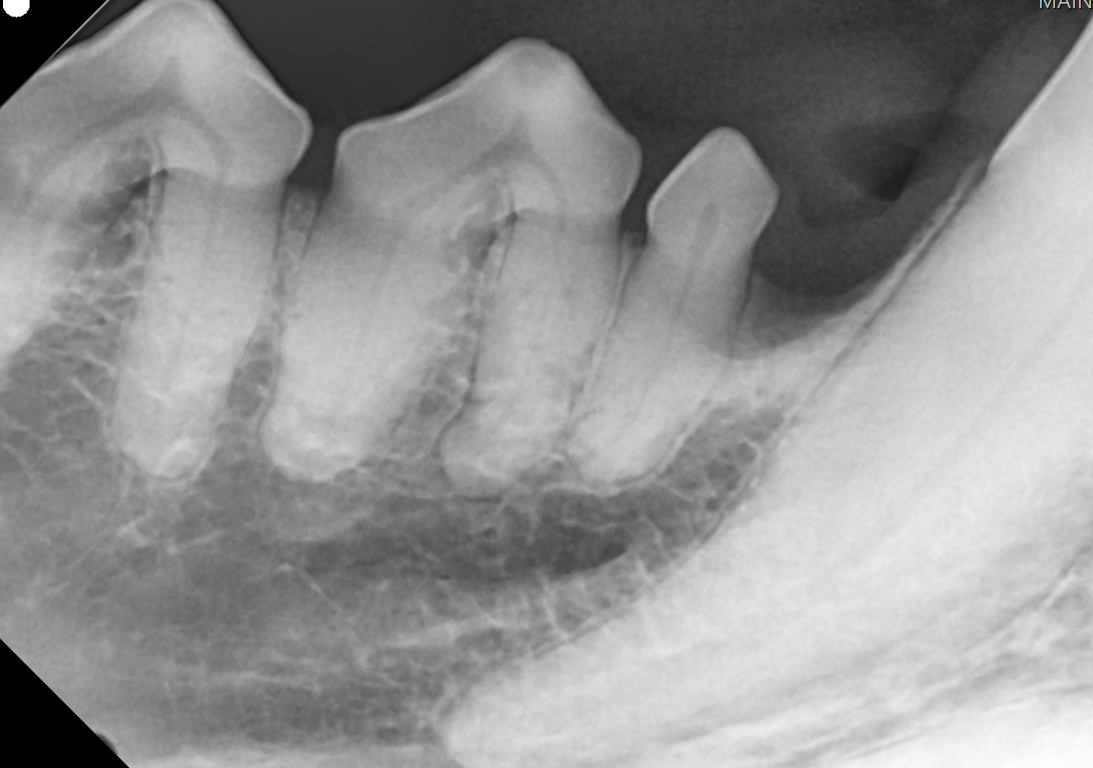

This X-Ray shows a not-so great situation for this pet.

We can actually even see the tartar buildup, which is really thick on all of these teeth. The bone is pulling away from that tooth. We can see these gaps in between the roots of the tooth. So this animal, essentially, instead of having a hundred percent of the root holding the tooth in, he's got. Maybe 20% that's holding on.